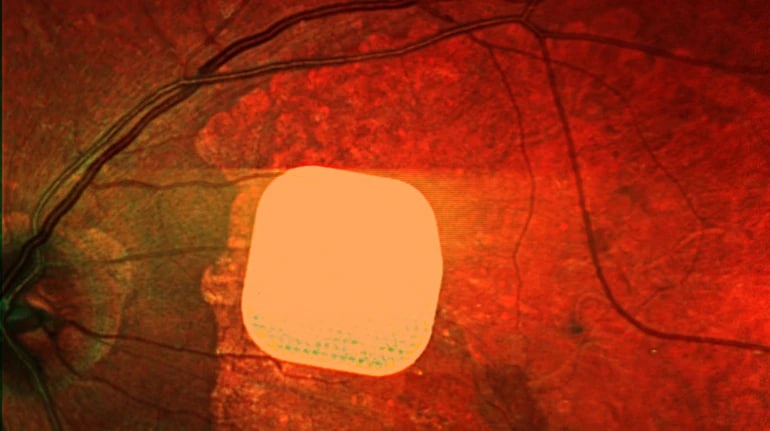

Лікарі з Великобританії зробили важливий крок у лікуванні вікової сліпоти. Вони успішно випробували новий електронний імплант Prima, який дозволяє частково відновити зір у пацієнтів із макулодистрофією – хворобою, яка призводить до втрати зору після 50 років. Мікрочип розміром всього 2×2 міліметри встановлюють під сітківку ока і підключають до системи окулярів доповненої реальності. Камера зчитує зображення, перетворює його на сигнал для мікрочипа, який активує клітини сітківки, що передають сигнал до мозку. У результаті дослідження 84% пацієнтів знову змогли розрізняти літери, цифри та слова після адаптації. Ця технологія відкриває нові можливості для людей з важкими зоровими проблемами, допомагаючи покращити їхню якість життя.

Британські лікарі частково повернули зір пацієнтам за допомогою мікрочипа